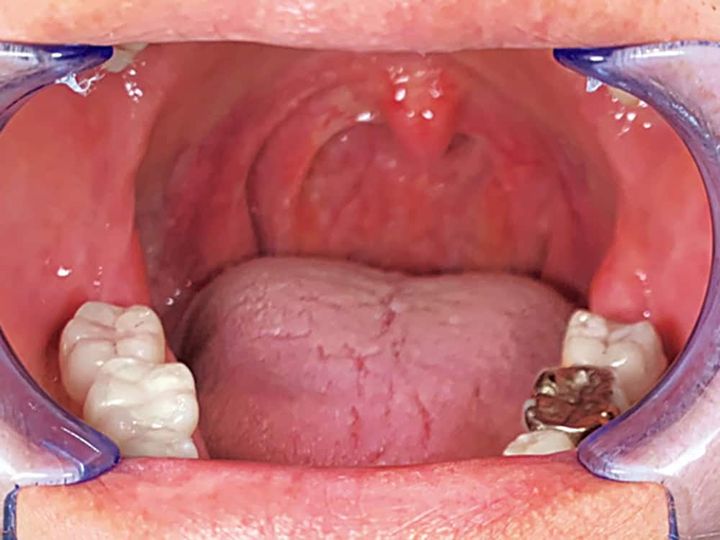

<1>

<2>

喉と舌の奥の筋肉をトレーニングすると、口蓋垂(喉ちんこのあたり)を鍛えられる。喉をしっかり上下させ音を鳴らして。

BEFORE

AFTER

全ての人が適用になるわけでないが、レーザー照射で緩んだ筋肉が引き締まると気道も確保しやすく。口腔筋トレーニングで引き締め効果が持続。